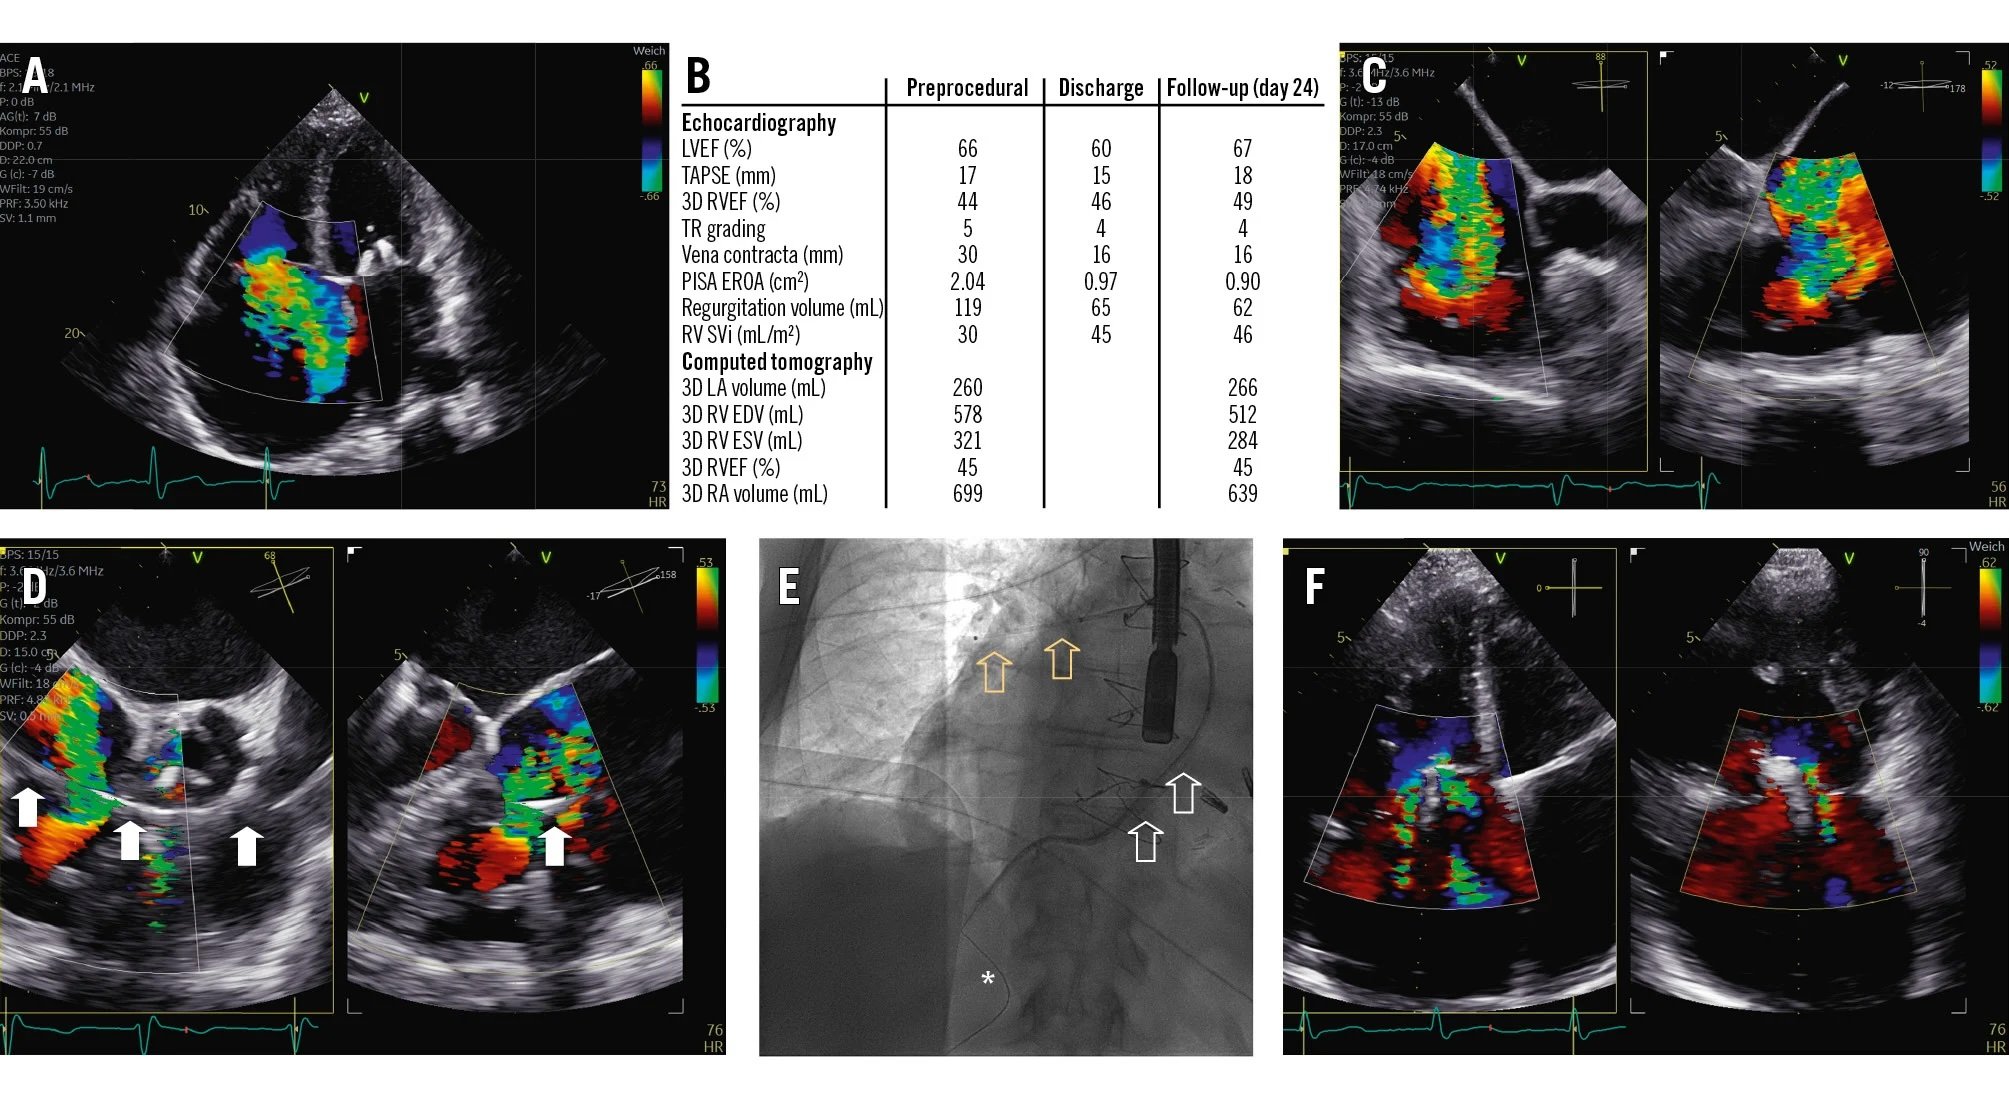

Outcomes of TEER for AFMR

This retrospective study analyzed 441 patients with functional mitral regurgitation who underwent transcatheter edge-to-edge repair. It found an association between optimal mitral regurgitation reduction, mean mitral valve pressure gradient, and clinical outcomes in patients with atrial functional mitral regurgitation.